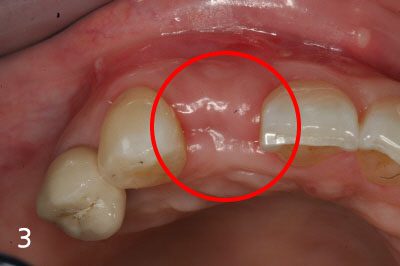

Performing implant placement and bone graft

Implant crown is fabricated after successful bone graft and implant placement